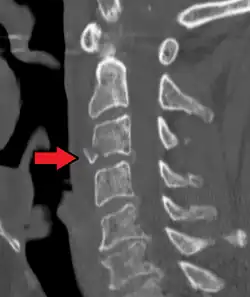

On CT scan or X-ray, a cervical fracture may be directly visualized. In addition, indirect signs of injury by the vertebral column are incongruities of the vertebral lines,[7] and/or increased thickness of the prevertebral space:[8]

-

X-ray of normal congruous vertebral lines -

![CT scan of normal congruous vertebral lines[7]](./_assets_/Vertebral_lines.png)